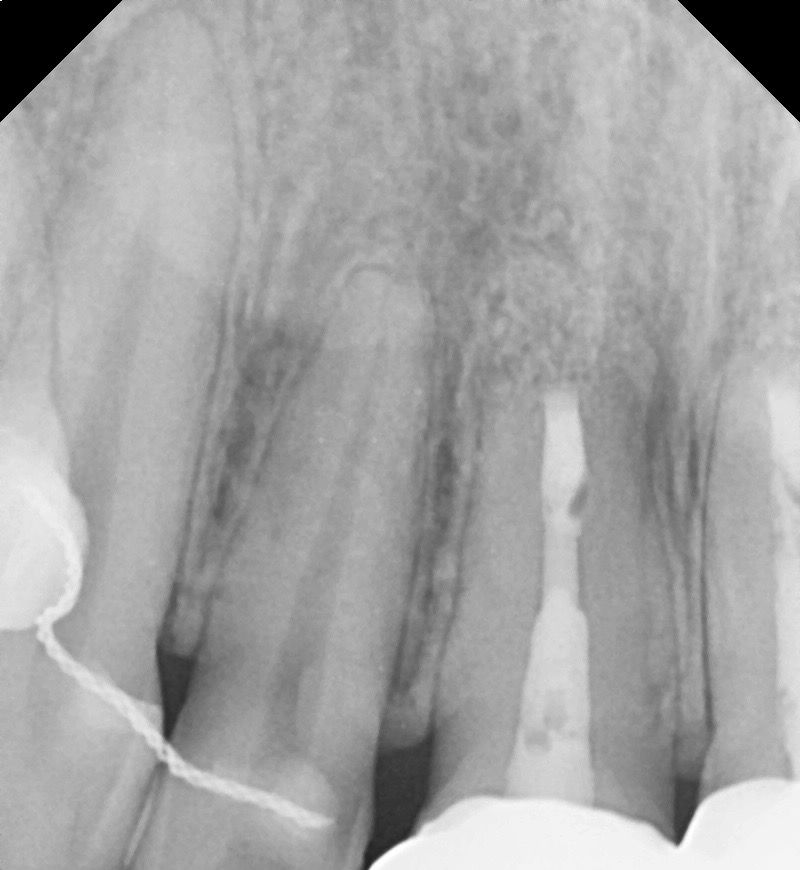

앞니 치근단절제술 해도 통증이 느껴집니다

우선 치근단절제술은 2년전에 다 끝낸 상태입니다..

크라운은 4년전에 브릿지로 씌웠고 요즘들어 크라운에서 냄새나고 잇몸이 검게 변했습니다

제가 궁금한건 치근단절제술을 한 치아인데도

그 치아가 욱신거리고 그 주변치아도 같이 욱신거립니다 치근단절제술 한 치아가 문제인건지 다른 정상치아가 문제인건지 통증이 생길땐 어떤치아가 아픈지 헷갈릴정도입니다..

오른쪽 대문앞니 (치근단수술한치아) , 그 옆 작은앞니, 그 옆 송곳니 까지 같이 욱신거리는데

치근단절제술 한 치아는 통증이 없어야 맞는건데 욱신거리는 통증이 느껴지는거면 문제있는걸까요?

잇몸이 문제라면 치근단절제술을 해도 통증이 느껴지나요? 주변치아가 아프니까 .. 어떤치아가 문제인지 도저히 모르겠습니다 ㅠㅠ

• 1번 째 사진